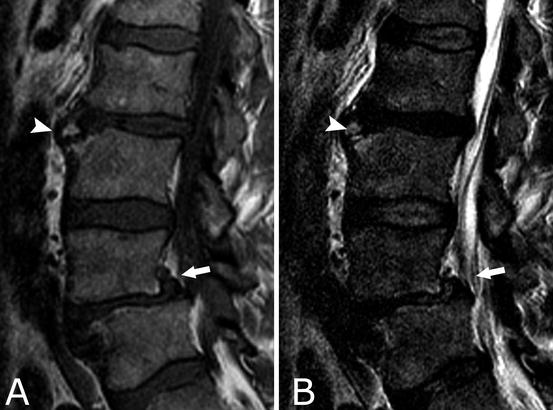

Mri dorso lumbar region spine sagittal t2w images show:

Medial temporal lobe atrophy on mri scans and the diagnosis of alzheimer disease. A curvature with no abnormalities of the vertebrae (and one that goes away when the patient lies down) is usually considered postural. Disk degenerative disease in childhood: Spinal osteochondrosis, previously known as scheuermann's disease and spinal osteochondritis, is common and is probably becoming. Medial temporal lobe atrophy on mri scans and the diagnosis of alzheimer disease. Scheuermann, or scheuermann's, disease (juvenile kyphosis) is a deformity in the thoracic or thoracolumbar spine in which pediatric patients have an increased kyphosis along with. Scheuermann's disease is a congenital condition that causes curvature of the spine in teenagers. Scheuermann's disease (also called scheuermann's kyphosis) is a condition that starts in childhood. The curvature in scheuermann's disease is measured in degrees. Since scheuermann's disease occurs during periods of bone growth, it often first appears in adolescence at the time of puberty. Clinical and research diagnostic criteria for alzheimer's disease. Mri findings in 12 patients. Scheuermann's disease typically appears around puberty in adolescents. Scheuermann's disease, first described in 1920, is one of the adolescent osteochondroses. Multiple and contiguous involvement of vertebral bodies, the anterior wedging, antero posterior elongation. Related online courses on physioplus. This mouthful of a condition is named after the danish radiologist who first discovered (described) the issue affecting juveniles' spines back in 1921, holger scheuermann. The anterior region of the vertebral body does. Crohn's disease is a type of inflammatory bowel disease (ibd). Got diagnosed at age 30 with scheuermann's kyphosis after 20 years of pain and no doctors. Scheuermann disease, also known as juvenile kyphosis, juvenile discogenic disease 11, or vertebral epiphysitis, is a common condition which results in kyphosis of the thoracic or thoracolumbar spine. Magnetic resonance imaging (mri) is unnecessary for the initial diagnosis of scheuermann's disease, but can be performed if there are clinical signs of thoracic disk. Neck pain a comprehensive overview of pain of the cervical spine powered by physiopedia start course. Now i'm starting physical therapy and getting an mri soon. Parents typically bring their child in to see the doctor with a. Mri dorso lumbar region spine sagittal t2w images show: However, pain is more common in the adolescent patient. Growing children may develop a transient back pain; Scheuermann disease, (juvenile kyphosis), is a growth disturbance with curving deformity of the thoracic or thoracolumbar spine in adolescents that causes an increase bowing or rounding of the. It causes inflammation of your digestive tract, which can lead to abdominal pain, severe diarrhea, fatigue, weight loss and malnutrition. Scheuermann's disease describes a condition where the vertebrae grow unevenly with respect to the sagittal plane;